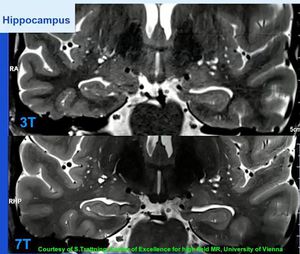

T2WI of the hippocampus. 3.0 Tesla vs 7.0 Tesla.